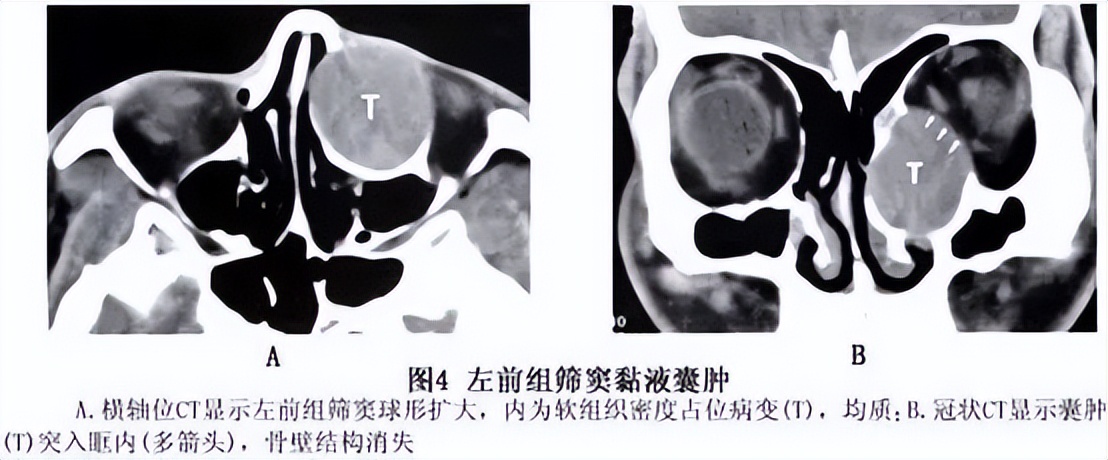

鼻窦黏液囊肿多发生在额窦和筛窦,蝶窦者较少,上颌窦最少,巨大的鼻窦黏液囊肿可侵入眶内和颅内。本病晚期并发感染,可转化为脓囊肿,其破坏性更大,可引起脑膜炎、脑脊液鼻漏或海绵窦血栓等。

鼻窦黏液囊肿的临床表现早期可无任何症状,以后黏液囊肿逐渐增大,压迫囊壁,引起头痛。若突入眶内可使眼球移位,并有复视、流泪、视力障碍等症状。囊肿发生于筛窦者眼球向外移位,发生于额窦者眼球向外下方移位。蝶窦黏液囊肿症状复杂,可致眼球突出,并压迫眶尖而致失明、眼肌麻痹、眼部感觉障碍和疼痛等症状,出现眶尖综合征。囊肿向上发展压迫脑垂体,可引起闭经、性欲减退、尿崩等内分泌失调现象,若压迫颈内动脉可致该动脉发生血栓。若蝶窦黏液囊肿向前壁破溃,黏液排出到鼻腔,以上症状暂时缓解。囊肿除了出现局部症状外还可以出现高热及周身不适等全身症状。